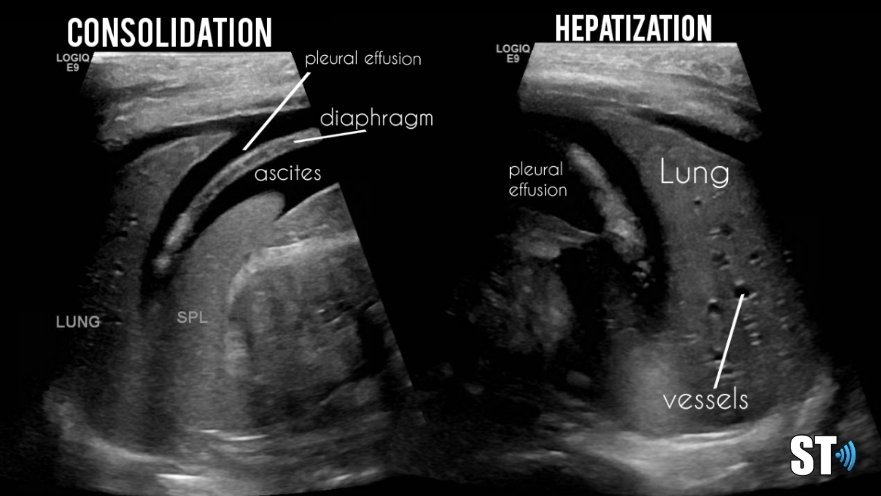

Consolidation

Hepatization of the lung parenchyma due to infiltration with fluid. May also have “air-bronchograms”.

In alveolar consolidation the lung parenchyma takes on the appearance of liver echotexture, “hepatization”. There may be air bronchograms present in consolidated tissue which appears as hyperechoic air bubbles with reverberation artifacts. Color doppler will show blood flow through the pulmonary vasculature.

Completely consolidated lung with pleural effusion and ascites